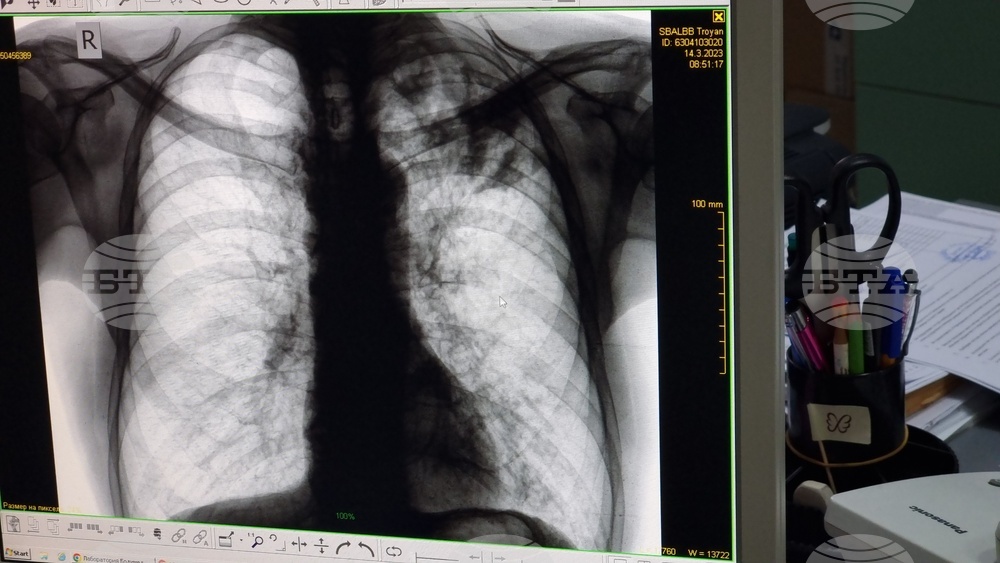

Университетска болница „Д-р Георги Странски“ в Плевен е инициатор на кампания за превенция на туберкулоза, информират от лечебното заведение. Тази инициатива ще се проведе от 2 до 6 декември в Отделението за диспансерно наблюдение на пациенти с белодробни заболявания, като е под мотото „Отворени врати за оценка на риска от белодробна туберкулоза“.

Всеки, който желае да участва, може да запише час за преглед както на място, така и чрез телефон 064/802 994. Прегледите ще се провеждат от 11:00 до 14:00 часа. Болницата подчертава, че всички прегледи в рамките на тази кампания ще бъдат напълно безплатни, независимо от здравноосигурителния статус на участниците. Препоръчва се жителите на областта с оплаквания от дихателната система или тези, които са били в контакт с болни от туберкулоза, да се възползват от възможността.